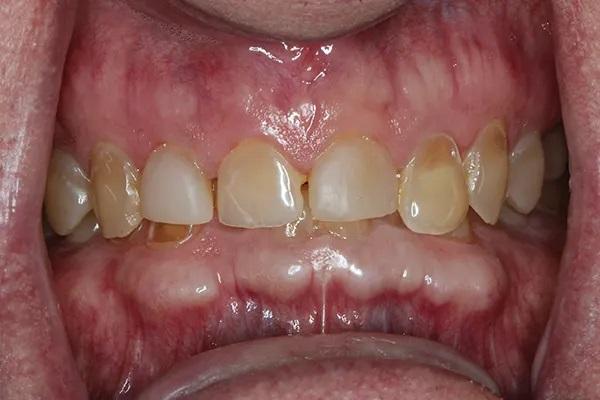

Мужчина, 54 года, был направлен к автору по поводу истирания зубных рядов и эрозии, которые, как предполагалось, были вызваны выраженным бруксизмом (Фото 1 и Фото 2). Его лечащий врач не был уверен, с чего начать планирование лечения, из-за предполагаемой сложности случая. Основной проблемой пациента был страх потерять часть или все зубы из-за обширного разрушения эмали (Фото 3). Были собраны снимки и подробные медицинские и стоматологические истории болезни, а также проведено детальное клиническое обследование. Полные снимки, фотографии и цифровые сканы были отправлены в зуботехническую лабораторию, и был разработан план лечения. У пациента было сильное желание действовать, и он принял этот план. Клинический случай был разбит на сегменты для обеспечения предсказуемой и более удобной реконструкции.

Фото 3: Передние зубы до лечения. Обратите внимание на сильное разрушение большинства зубов пациента.